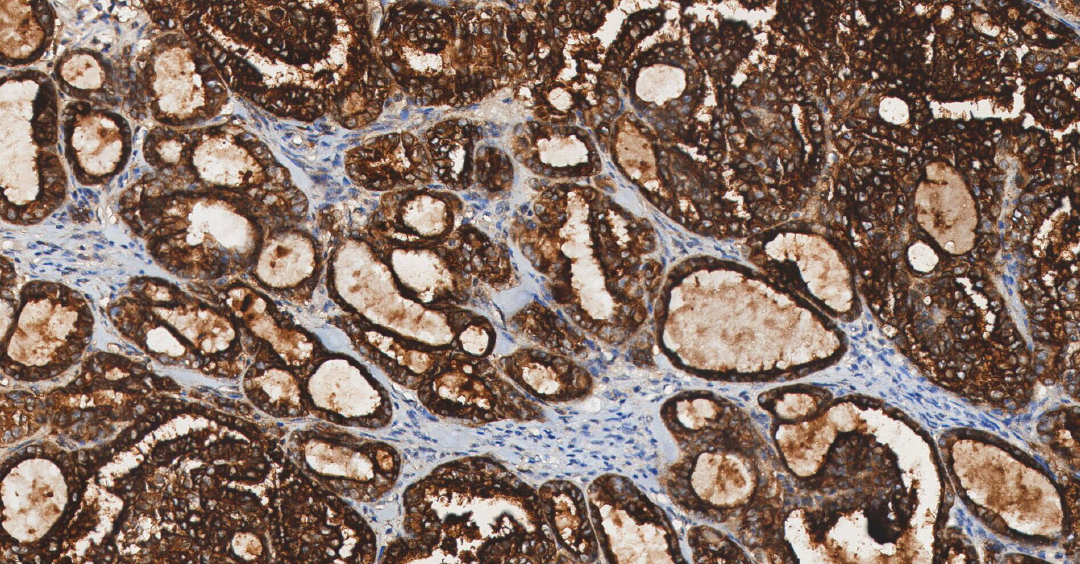

HER2

HER2——人表皮生长因子受体 2,属于表皮生长因子受体家族。

定位: 细胞膜。

功能: HER2 是一种具有酪氨酸激酶活性的跨膜蛋白,但无已知配体。它通常与其他家族成员形成异二聚体,参与传递调控细胞生长和分化的信号[9]。

大约 20-30% 的乳腺癌存在 HER2 基因扩增,从而使细胞膜上 HER2 蛋白的显著过表达。 这引发强烈的、持续的下游促增殖信号,导致侵袭性更强的肿瘤表型[10]。此外,HER2 的过表达或突变与胃癌、胃食管癌、肺癌、子宫内膜癌及卵巢癌也密切相关[11]。

图 6. 人乳腺癌组织的 HER2 免疫组化分析 (HY-P80658)。